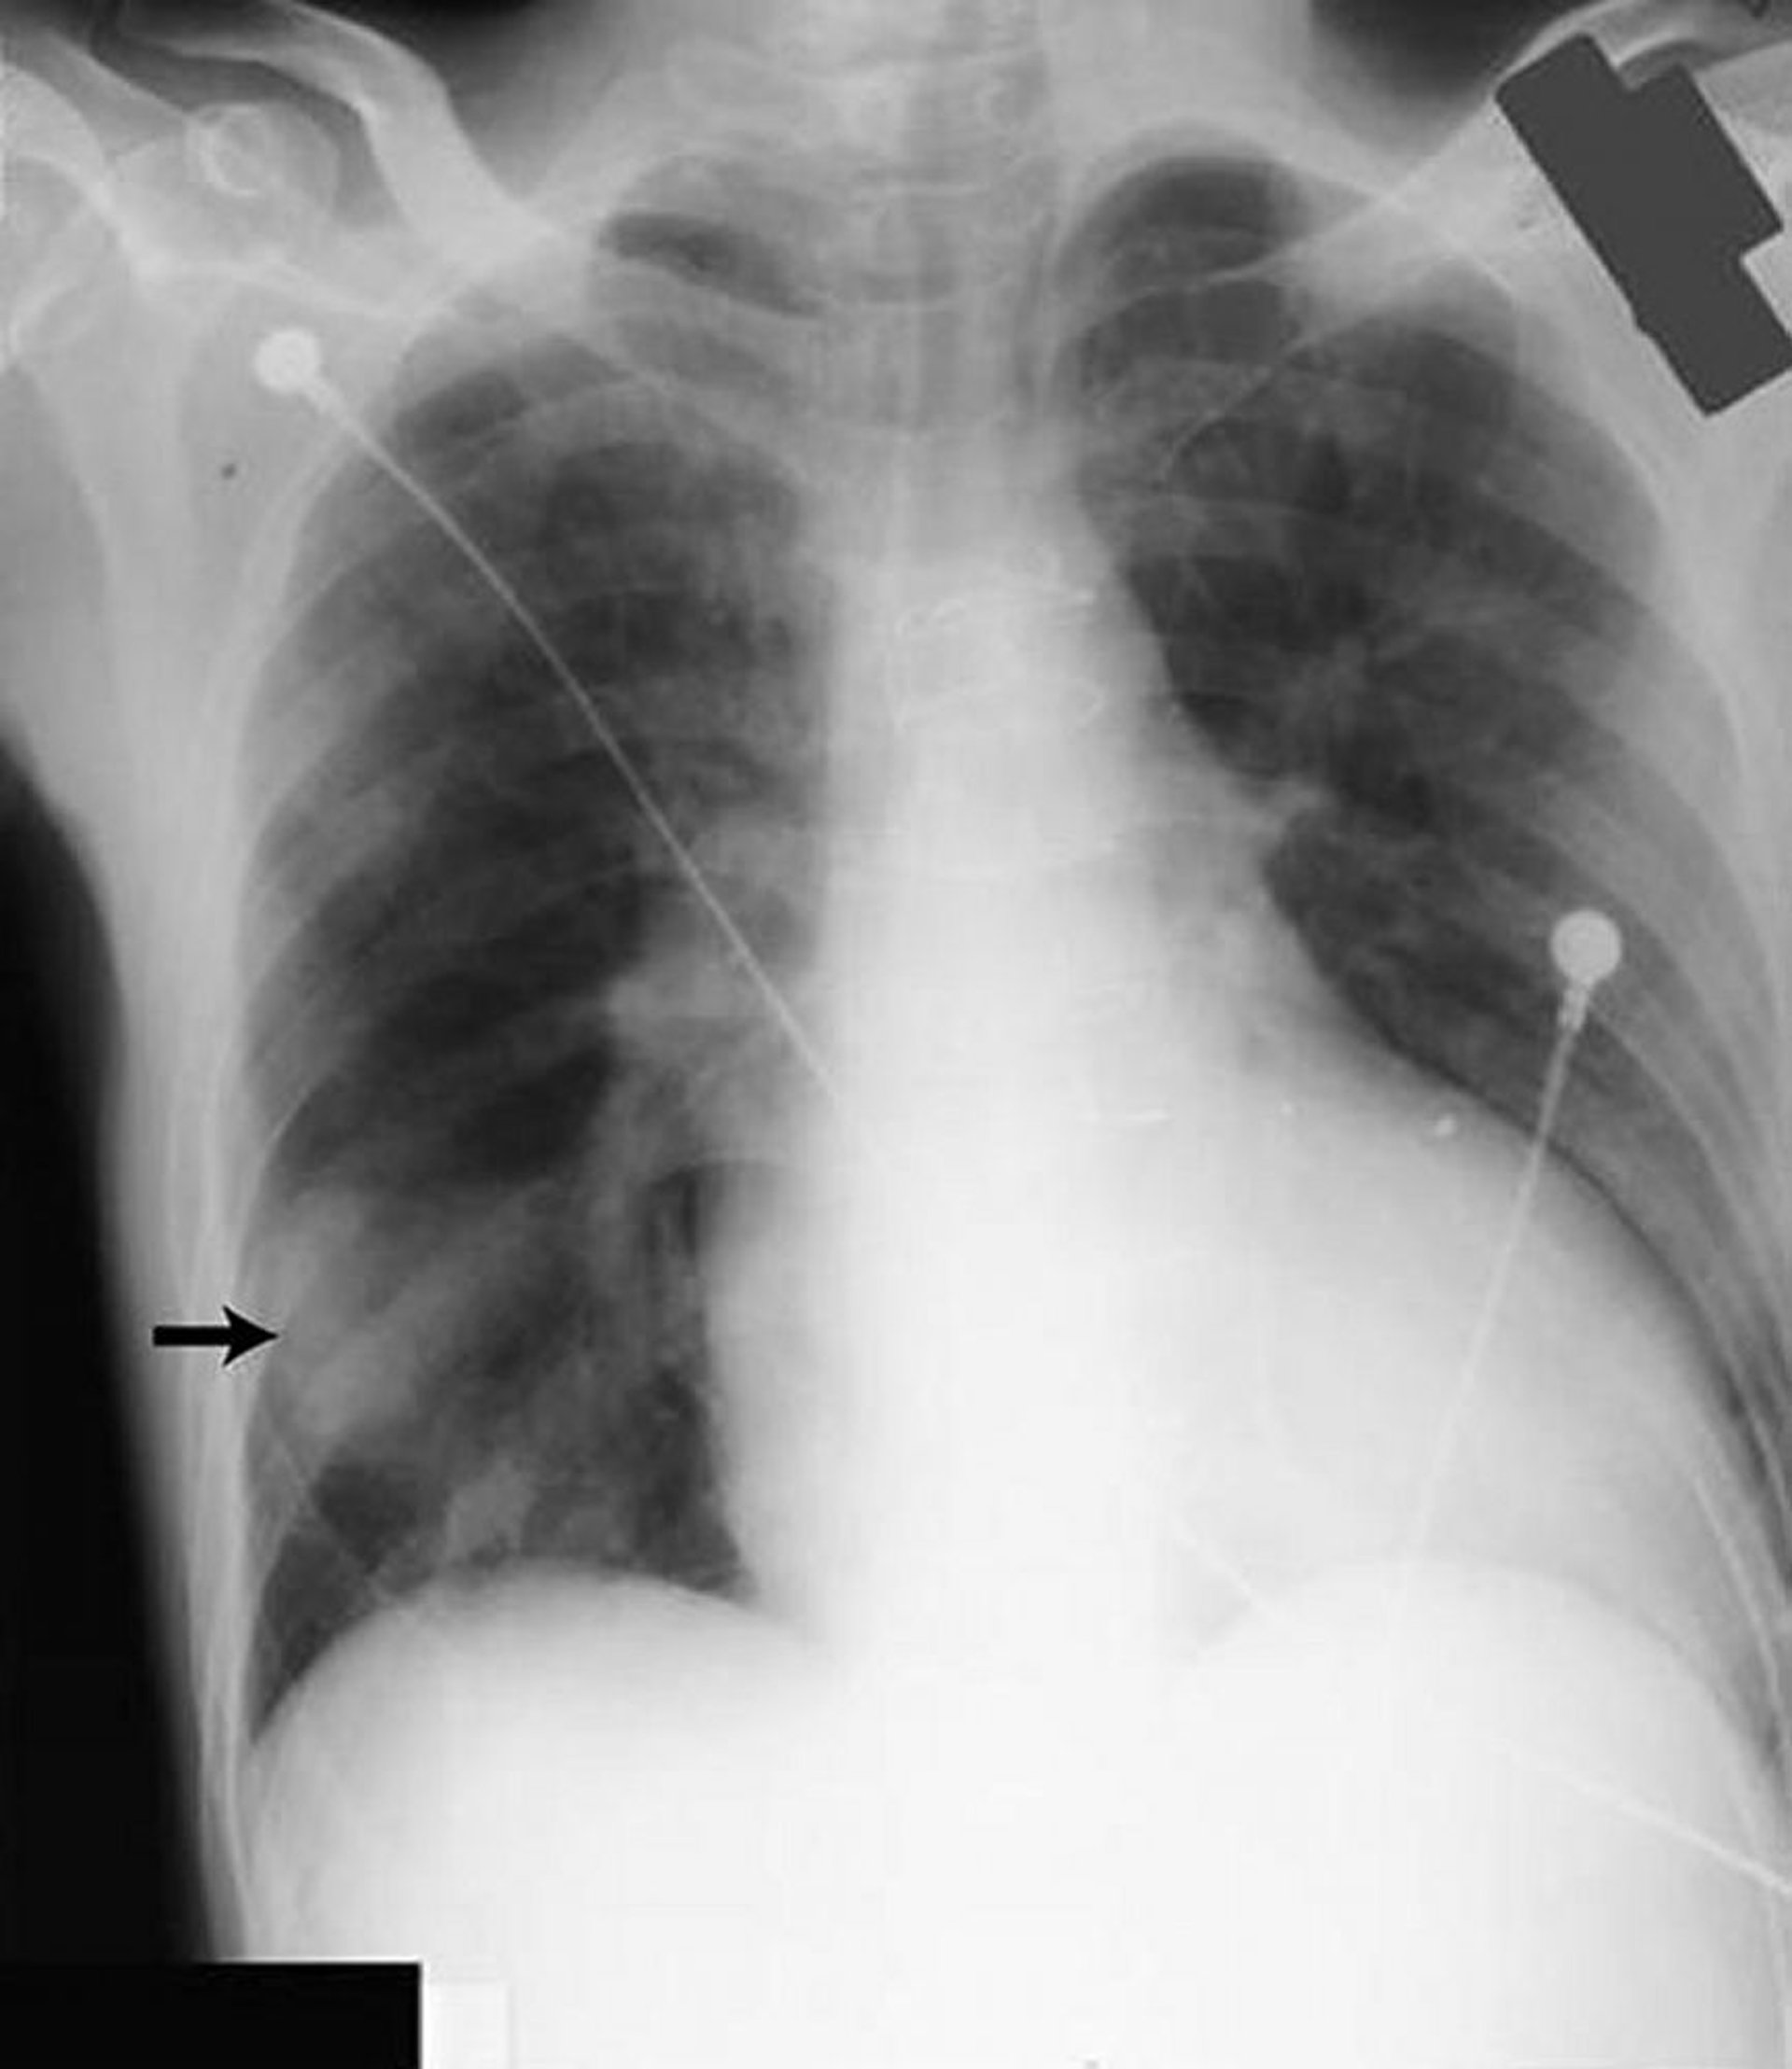

Pseudotumeur pulmonaire

L'opacité dans le champ pulmonaire inférieur droit (flèche) ressemble à une masse solide mais a été provoquée par du liquide dans la grande scissure chez un patient souffrant d'insuffisance cardiaque.